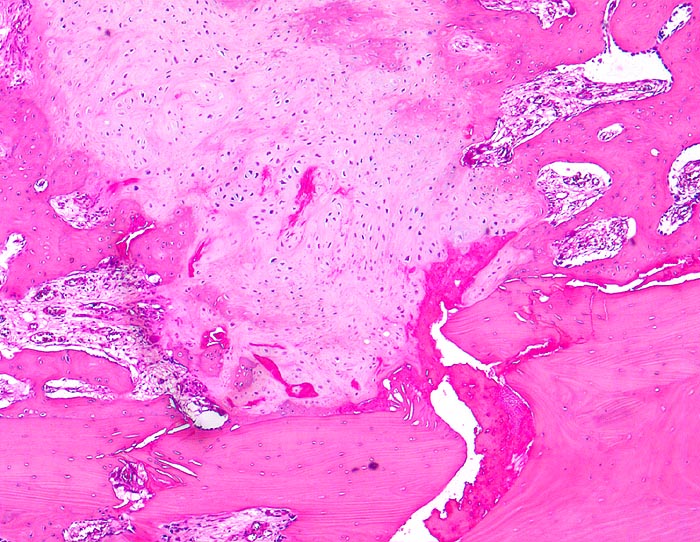

sekundäre Frakturheilung: Frakturspalt

Knochen, Rippe

Frakturspalt mit Fibrinablagerungen und neugebildetem, teils mineralisiertem Knorpel. Devitalisierter ortsständiger Knochen mit leeren Osteozytenhöhlen. Markraumfibrose.

Konservativ behandelte Rippenfraktur nach Sturz vor einem Monat.

Der Nachweis von neugebildetem Knorpel entlang der Frakturlinie im Innern des Knochens ist ein Charakteristikum vor allem der Rippenfraktur als Folge einer mangelhaften Ruhigstellung. Die notwendige Resorption des avitalen Knochens führt zu einer Heilungsverzögerung.